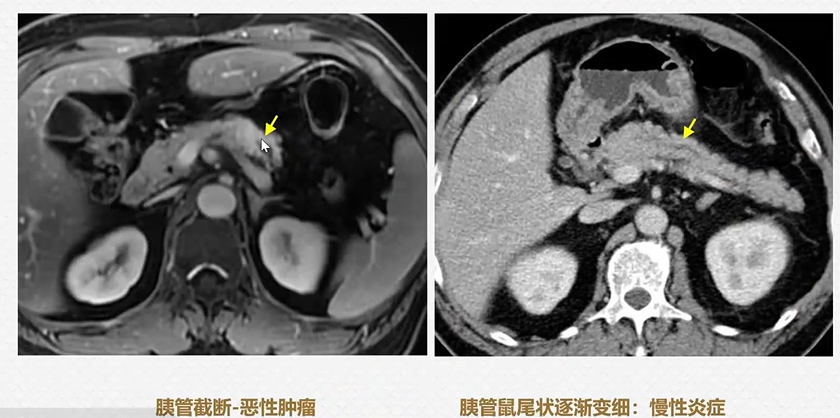

2. 胰管截断征

胰体癌造成的胰管截断,有助诊断。

8.腊肠征

9.刀鞘征

自身免疫性胰腺炎,腊肠征-刀鞘征

图14 腊肠征-刀鞘征

(图片来源:余日胜教授讲课使用)

10.胰管鼠尾征

胰管轻度扩张且慢慢变细,为良性特征。慢性胰腺炎。

图15 胰管截断征与鼠尾征对比